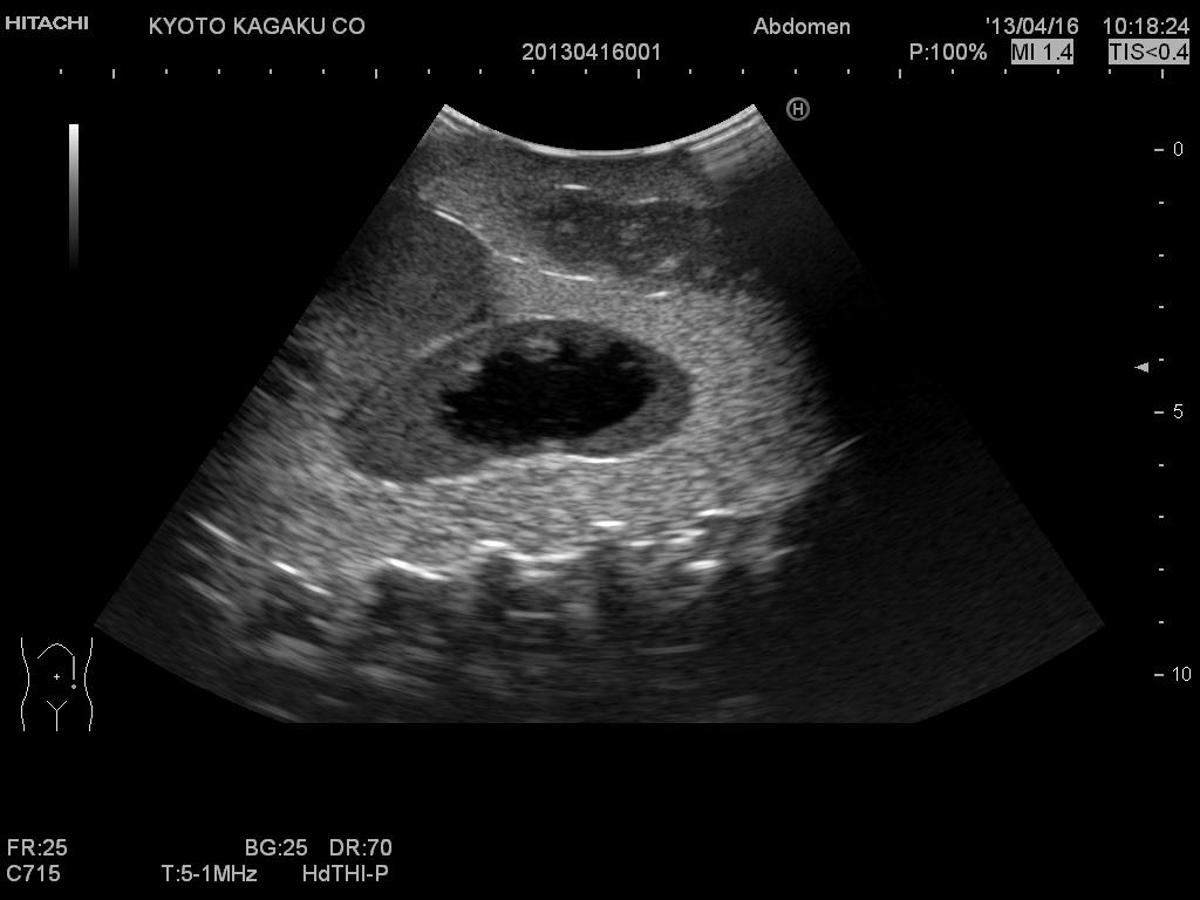

The Paediatric FAST/Acute Abdomen Phantom facilitates the practice of hands-on training using ultrasound to examine young patients. Using FAST procedures, trainees are able to identify internal haemorrhage at the perihepatic, perisplenic, pelvis, and pericardium area, whilst the ultrasound capabilities of the module allow for bowel intussusception, appendicitis and biliary dilatation recognition.

Sonography for acute paediatric patient, helping to identify bowel intussusception, appendicitis and biliary dilatation